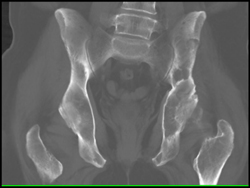

CTA Thigh S/P Stab Wound